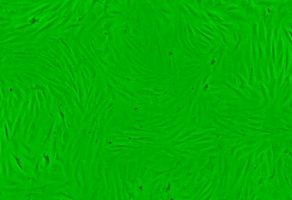

贴壁;上皮细胞样

形 态:贴壁;上皮细胞样

每天定时观察OV-90细胞生长情况,一般72-96h后,细胞生长密度大于90%,即可进行细胞的传代或保株。